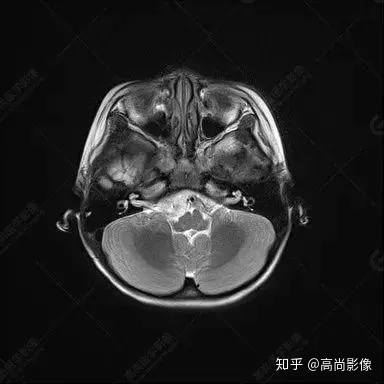

右側(cè)顳葉腫瘤切除術(shù)后(具體不詳):右側(cè)顳部骨質(zhì)不連續(xù)呈術(shù)后改變,右側(cè)顳葉術(shù)區(qū)見片狀長(zhǎng)T1長(zhǎng)T2信號(hào)影,F(xiàn)LAIR呈低信號(hào);術(shù)區(qū)后方右側(cè)顳枕葉見一巨大占位性病變影,邊界欠清,大小約6.2×5.8×4.3cm(前后×左右×上下),信號(hào)不均勻,T1WI呈等稍低信號(hào)間雜少許高信號(hào),T2WI呈高稍低混雜信號(hào),DWI示部分病灶彌散受限,相應(yīng)ADC圖減低,磁敏感序列見部分呈極低信號(hào),增強(qiáng)掃描可見明顯不均勻強(qiáng)化,鄰近硬腦膜及小腦幕增厚并明顯強(qiáng)化;另延髓右前方及右側(cè)橋小腦角區(qū)見一不規(guī)則形異常信號(hào)影,大小約3.2×1.3×3.7cm(左右×前后×上下),呈長(zhǎng)T1稍長(zhǎng)T2信號(hào),F(xiàn)LAIR呈等信號(hào),DWI未見受限,增強(qiáng)后明顯均勻強(qiáng)化,鄰近腦膜明顯強(qiáng)化。鄰近腦實(shí)質(zhì)及右側(cè)顳角明顯受壓;左側(cè)大腦半球未見局灶性信號(hào)異常,中線結(jié)構(gòu)稍左移。

右側(cè)顳葉腫瘤切除術(shù)后:現(xiàn)術(shù)區(qū)后方右側(cè)顳枕葉及延髓右前方占位,右側(cè)顳枕部硬腦膜及小腦幕明顯強(qiáng)化,結(jié)合既往影像資料,考慮為胚胎源性惡性腫瘤,如非典型畸胎樣/橫紋肌樣瘤(AT/RT)或原始神經(jīng)外胚層腫瘤(PNET)。